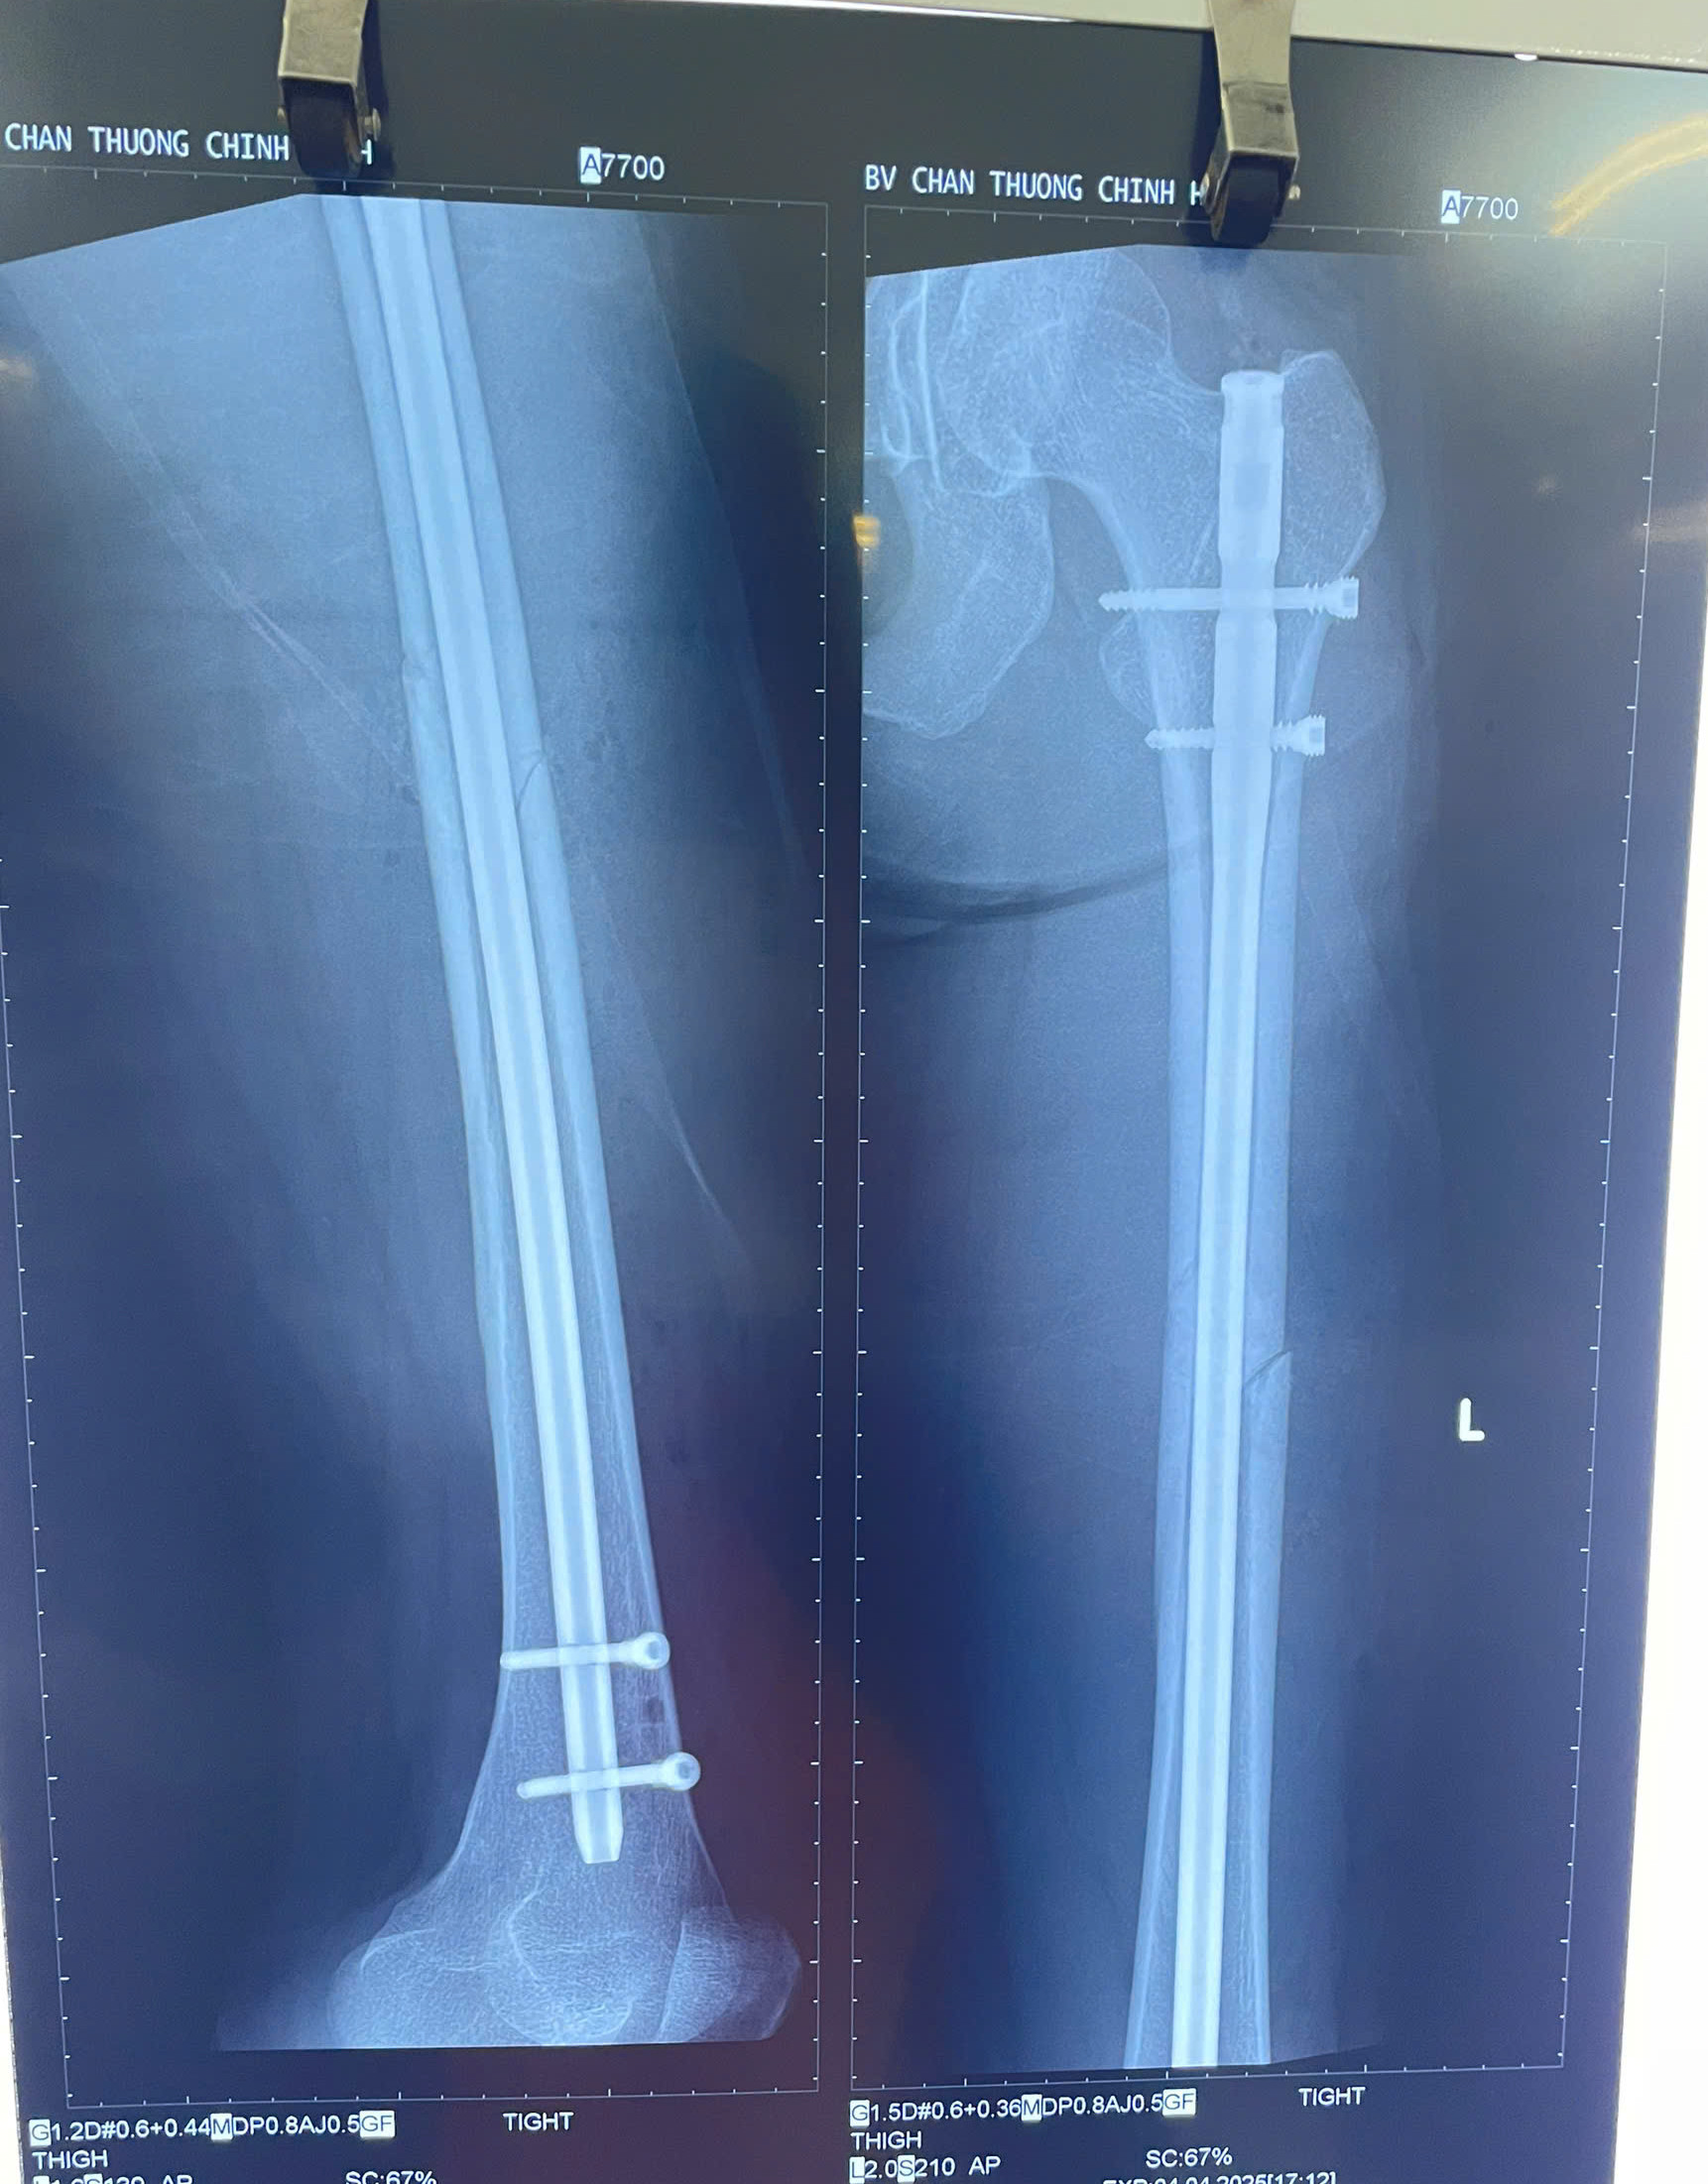

Hình ảnh chụp X-quang của bệnh nhân sau phẫu thuật đóng đinh chốt đùi

Qua thăm khám, chụp X-quang, bác sĩ xác định cô bị gãy 1/3 giữa thân xương đùi bên trái. Sau đó, bệnh nhân được bác sĩ phẫu thuật khẩn cấp.

Với tình trạng gãy xương và mong muốn sớm quay lại sân chơi thể thao, các bác sĩ đã cân nhắc một phương pháp mổ với đường mổ nhỏ, đóng đinh xương đùi với chốt 2 đầu xương đùi, đảm bảo không ảnh hưởng quá nhiều đến thẩm mỹ. Sau phẫu thuật, Kỳ Hân sẽ cần thời gian để phục hồi, và dự kiến phải mất ít nhất 6 tháng trước khi cô có thể quay lại thi đấu.